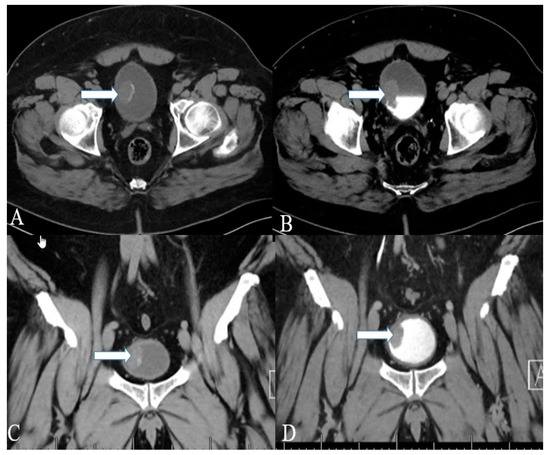

Figure 13. A 48-year-old female with ureteral NENs. (A) Coronal T2 nonfat sat image shows a large expansible hematoma in the ureteric stump (arrows). (B) Coronal T1 postcontrast delayed fat sat image: Shows a large expansible hematoma with intrinsic high T1 signal. (C) Axial T1 postcontrast delayed fat sat subtraction image: a small enhancing nodule (arrows) along the superior aspect of the stump. (D) Left lower ureter mass consists of a segment of the ureter with an attached firm, tan-brown, irregular, mass, measuring 11.5 × 7.0 × 6.0 cm. (E) E&H staining: 20× shows polypoid tumor bulging into the ureter lumen. Normal urothelial mucosa and muscle layer can be seen on the top half (arrow). (F) H&E straining: 200× high-power view shows tumor cells arranged in a trabecular and tubular pattern. (G) Synaptophysin staining: 200× shows tumor cells expressing synaptophysin (brown staining), which is a marker of neuroendocrine differentiation.